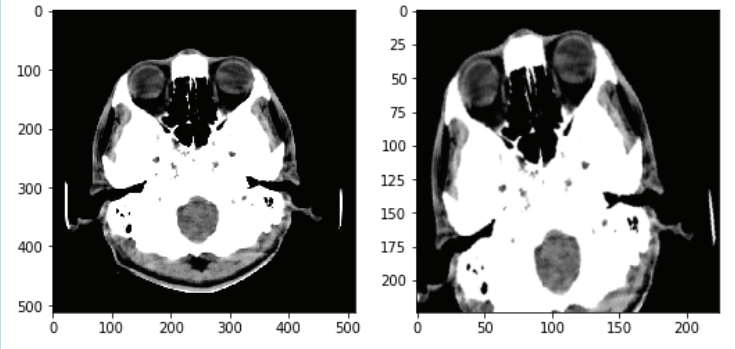

An example can be seen in figure 1

Refer to caption

Figure 1: Original image(left) vs random augmented image(right)